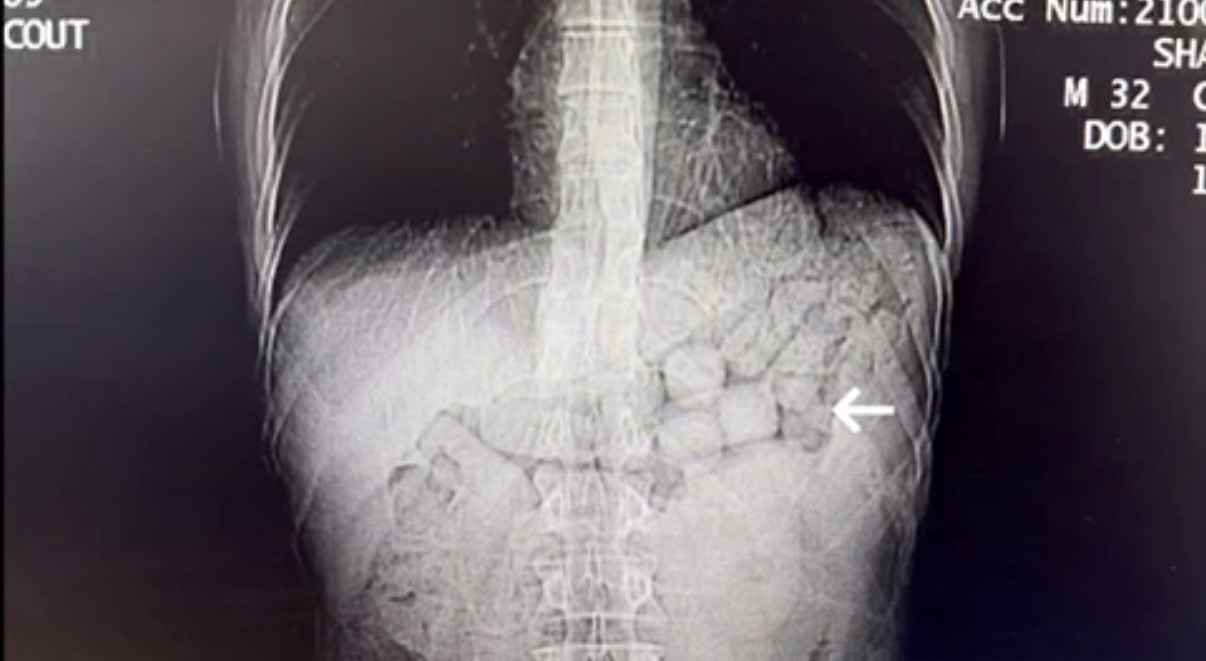

Bahse konu şahısların çekilen tomografi görüntülerinde, mide ve bağırsak bölümlerinde yabancı cisimlere rastlandı.

Yaklaşık 3 gün süren kontroller sonucunda şahıslardan; 91 kapsül halinde 807,15 gram Metamfetamin maddesi ele geçirildi ve şüpheliler gözaltına alındı.